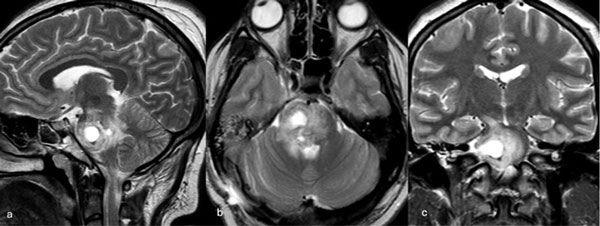

Una paciente femenina de 28 años, sin antecedentes de sangrado previo, debutó con cefalea, náuseas y vómitos, asociado a diplopía secundaria a una parálisis del VI par derecho. La RM de encéfalo evidenció una malformación cavernomatosa centrada en puente y el pedúnculo cerebeloso medio derecho (Figura 3). Un mes después del sangrado, se realizó una exéresis de la lesión mediante un abordaje retrosigmoideo ampliado a través del pedúnculo cerebeloso medio (Figura 4), logrando una exéresis completa (Figura 5). Tras el procedimiento, la paciente evolucionó con hemihipoestesia del hemicuerpo izquierdo, sin otros síntomas agregados.

Figura 3. RM preoperatoria de encéfalo. Se evidencia una lesión única intraaxial centrada en puente y pedúnculo cerebeloso derecho, sugerente de un cavernoma roto. A, B y C) Imágenes ponderadas en T2 en cortes sagital, axial y coronal, respectivamente, donde se observa un importante hiperintensidad perilesional, sugerente de edema.

Figura 4. Imágenes intraoperatorias bajo microscopía. Abordaje retrosigmoideo ampliado a derecha, con ruta de ingreso transpedúnculo cerebeloso medio. A yB) Corticotomía en pedúnculo cerebeloso medio. C) Identificación y resección en bloque de la malformación cavernomatosa. D) Revisión del lecho, sin remanente.

Figura 5. RM postquirúrgica de encéfalo. Se evidencia una exéresis completa con hiperintensidad en T2 en regresión. A, B y C) Imágenes ponderadas en T2 en cortes coronal, axial y sagital, respectivamente.